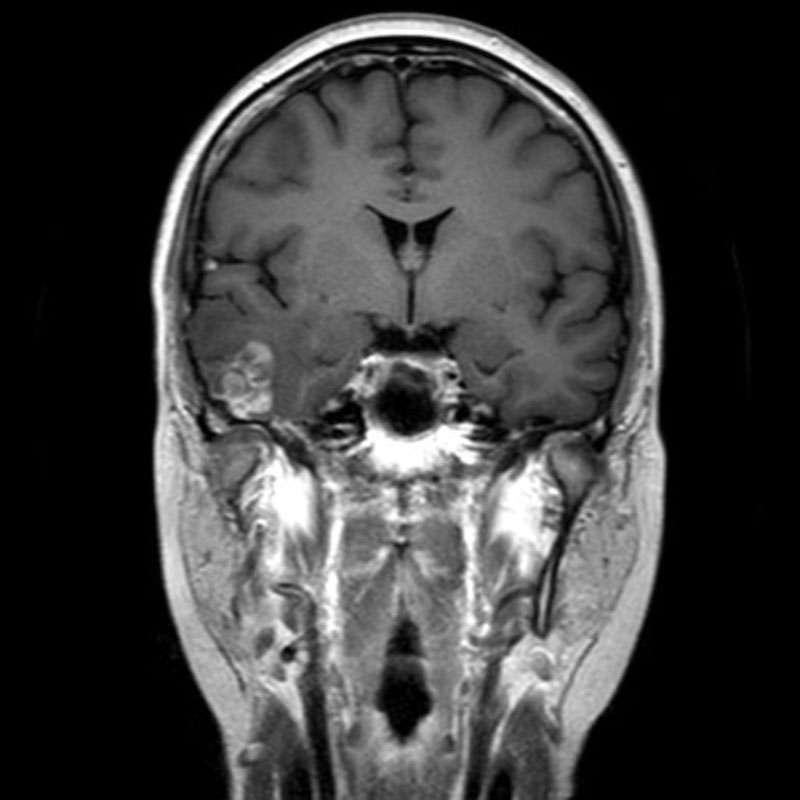

下垂体腺腫

頭蓋内腫瘍摘出術

No.’25_102 手術前1

No.’25_102 手術前2